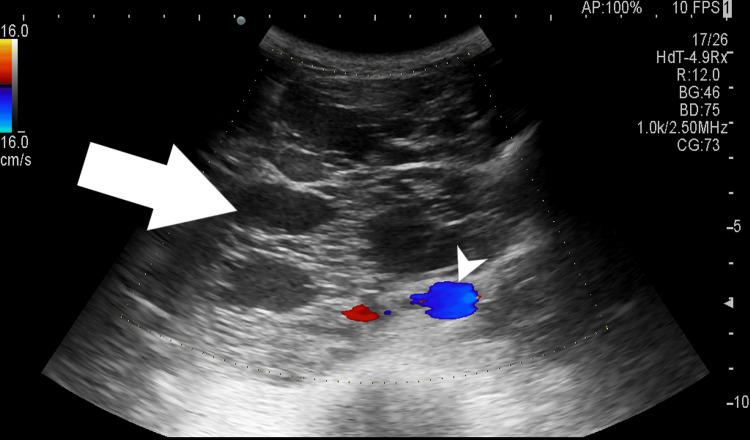

Growing teratoma syndrome (GTS) represents a rare yet significant complication following treatment for non-seminomatous germ cell tumors (NSGCT), characterized by the growth of mature teratoma elements despite prior chemotherapy. We present the case of a 30-year-old male who, following orchidectomy for NSGCT and subsequent chemotherapy, developed acute abdominal pain and pulmonary metastasis. Despite normal serum tumor markers, imaging revealed a large retroperitoneal mass encasing significant vessels. Surgical excision led to symptom resolution. This case underscores the diagnostic challenges GTS poses, the importance of imaging in diagnosis, and the efficacy of prompt surgical intervention in achieving favorable outcomes.

成熟性畸胎瘤综合征(GTS)是非精原细胞性生殖细胞肿瘤(NSGCT)治疗后一种罕见但严重的并发症,其特征是尽管先前进行了化疗,但仍有成熟畸胎瘤成分生长。我们报告了一例30岁男性病例,该患者因NSGCT接受睾丸切除术后并进行了后续化疗,出现了急性腹痛和肺转移。尽管血清肿瘤标志物正常,但影像学检查显示一个巨大的腹膜后肿块包绕了重要血管。手术切除后症状得以缓解。该病例强调了GTS带来的诊断挑战、影像学在诊断中的重要性以及及时手术干预在取得良好预后方面的有效性。